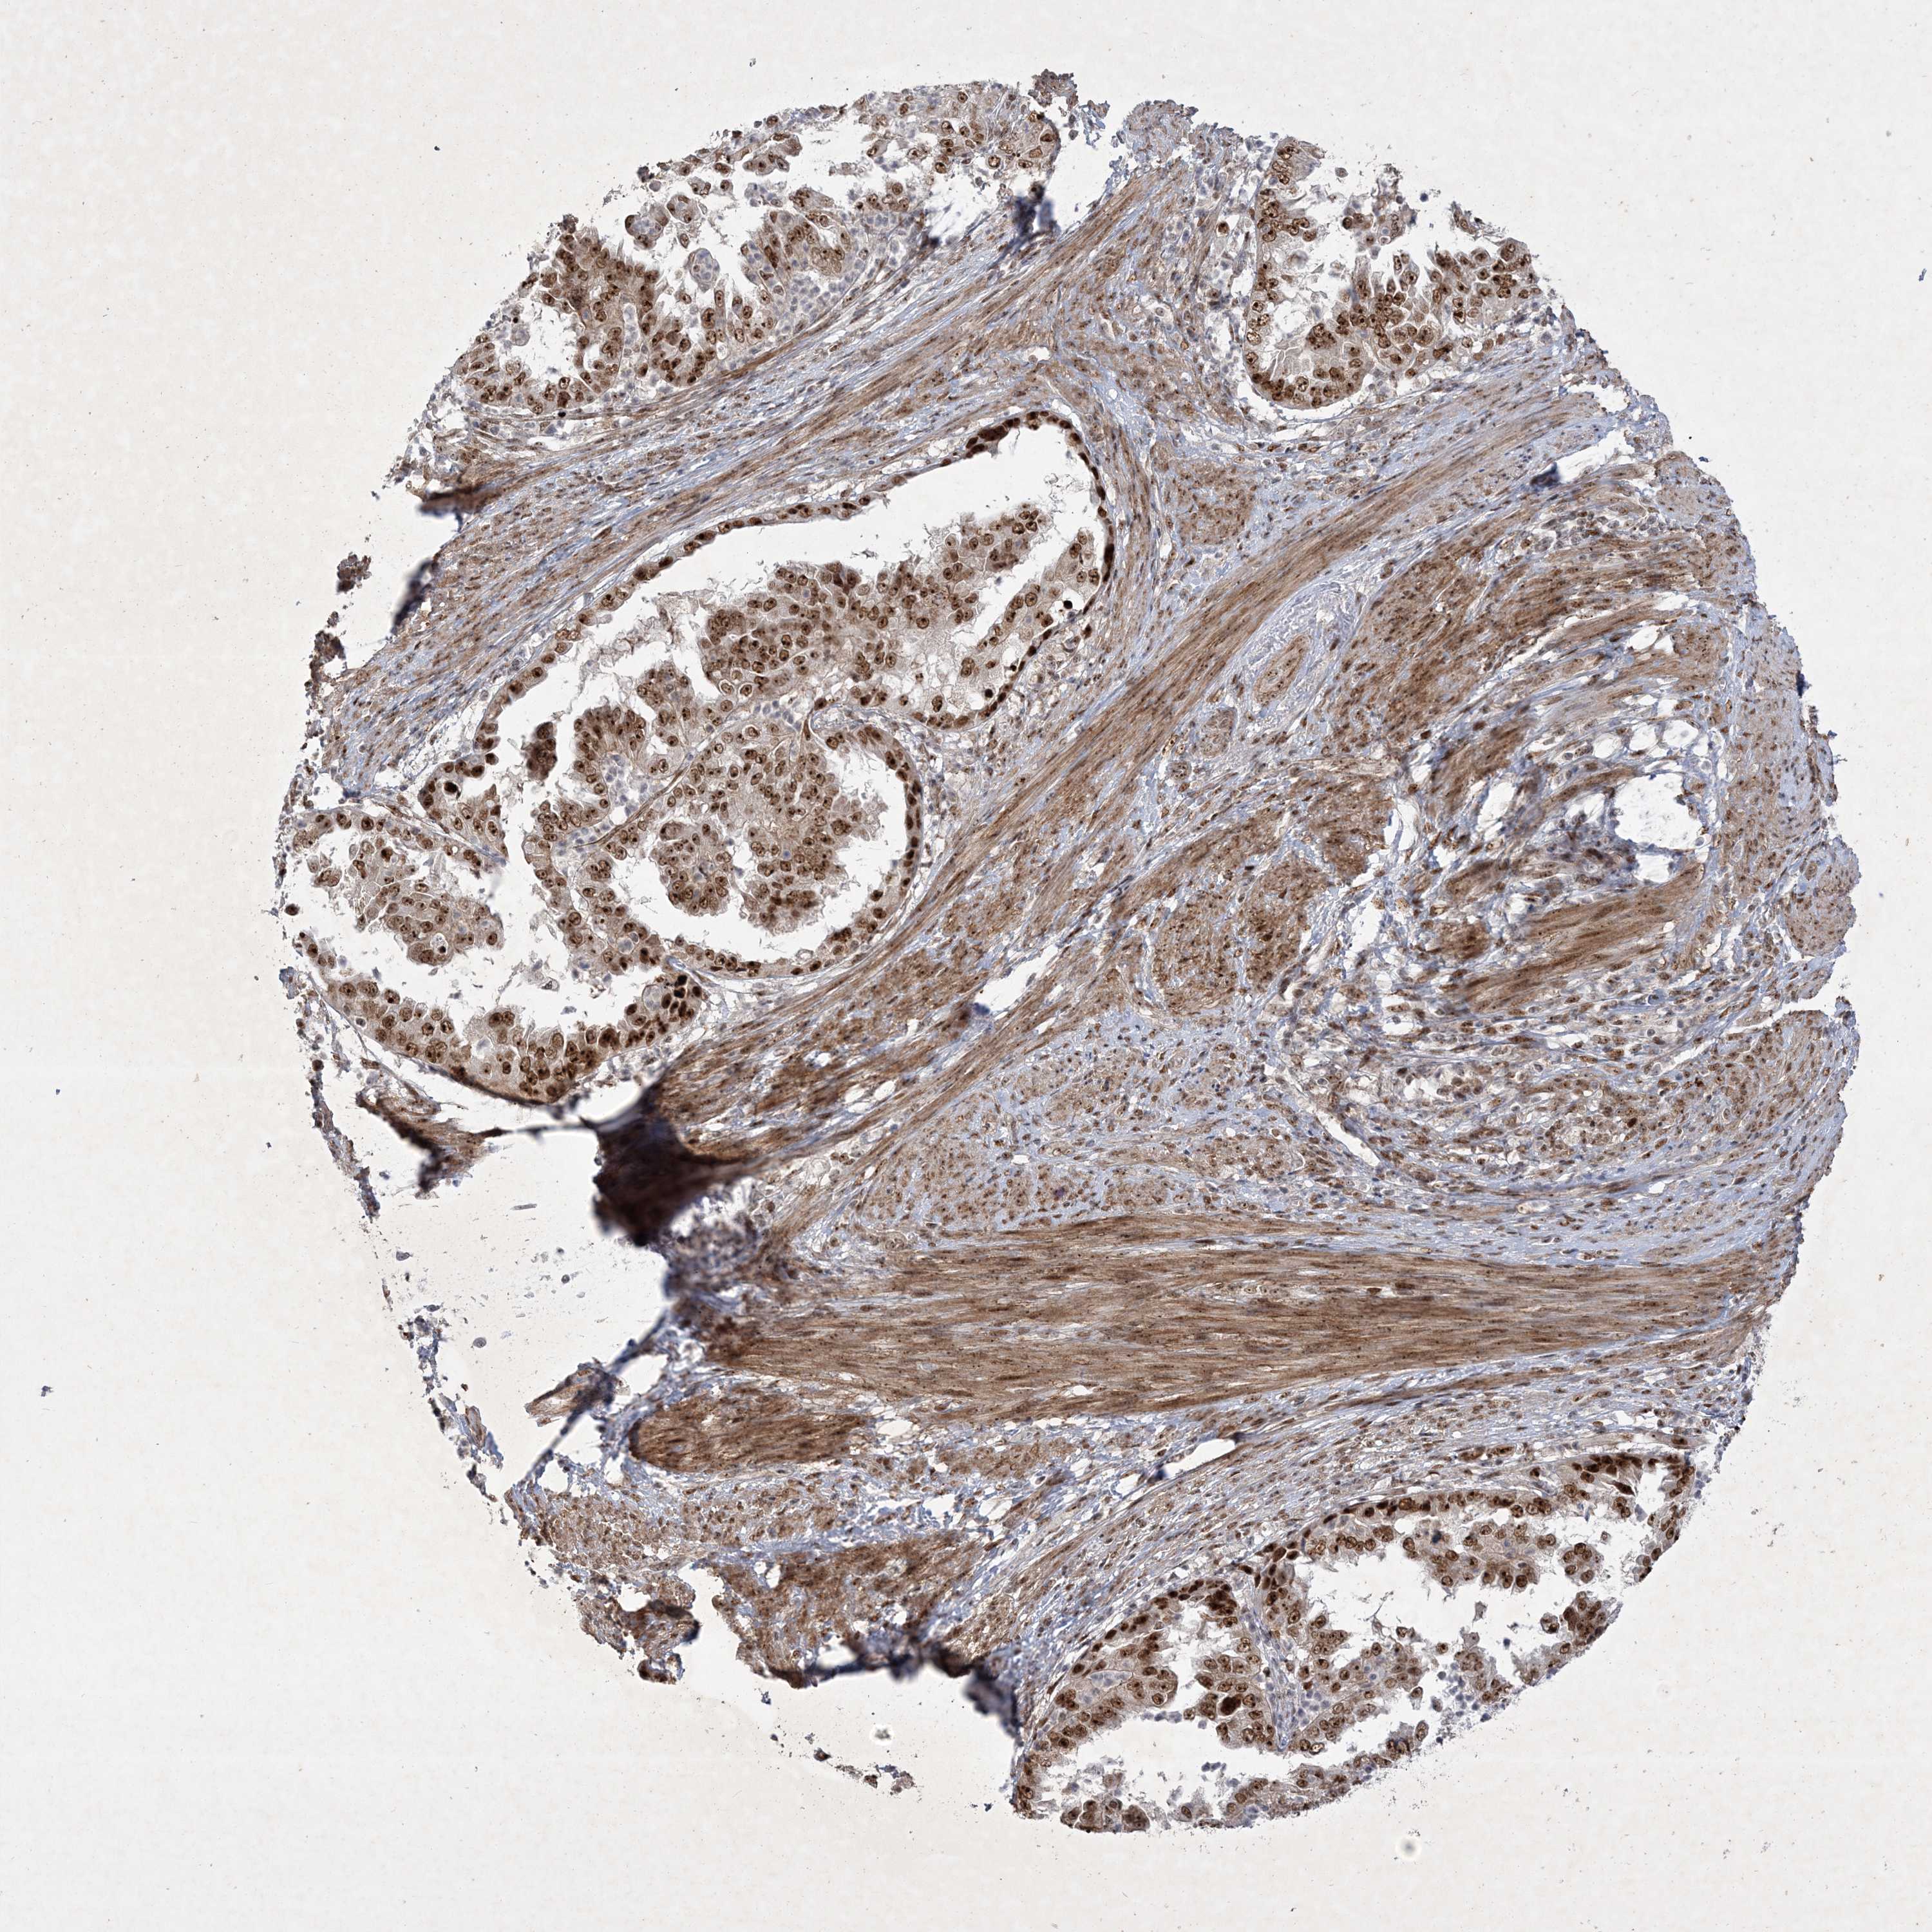

ENDOMETRIAL CANCER - Protein expressioni

A mouse-over function shows sample information and annotation data. Click on an image to view it in a full screen mode. Samples can be filtered based on level of antibody staining by selecting one or several of the following categories: high, medium, low and not detected. The assay and annotation is described here.

Note that samples used for immunohistochemistry by the Human Protein Atlas do not correspond to samples in the TCGA dataset.

Antibody stainingi

Antibody staining in the annotated cell types in the current human tissue is reported as not detected, low, medium, or high, based on conventional immunohistochemistry profiling in selected tissues. This score is based on the combination of the staining intensity and fraction of stained cells.

Each image is clickable and will lead to virtual microscopy that enables deeper exploration of all samples and also displays staining intensity scores, fraction scores and subcellular localization as well as patient and tissue information for each sample.

Antibody HPA036295

Antibody HPA036296

Staining

High

Medium

Low

Not detected

Intensity

Strong

Moderate

Weak

Negative

Quantity

>75%

75%-25%

<25%

None

Location

Nuclear

Cytoplasmic/membranous

Cytoplasmic/membranous,nuclear

Adenocarcinoma, metastatic, NOS